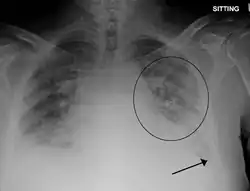

A chest x-ray showing pulmonary edema with bilateral pleural effusions.